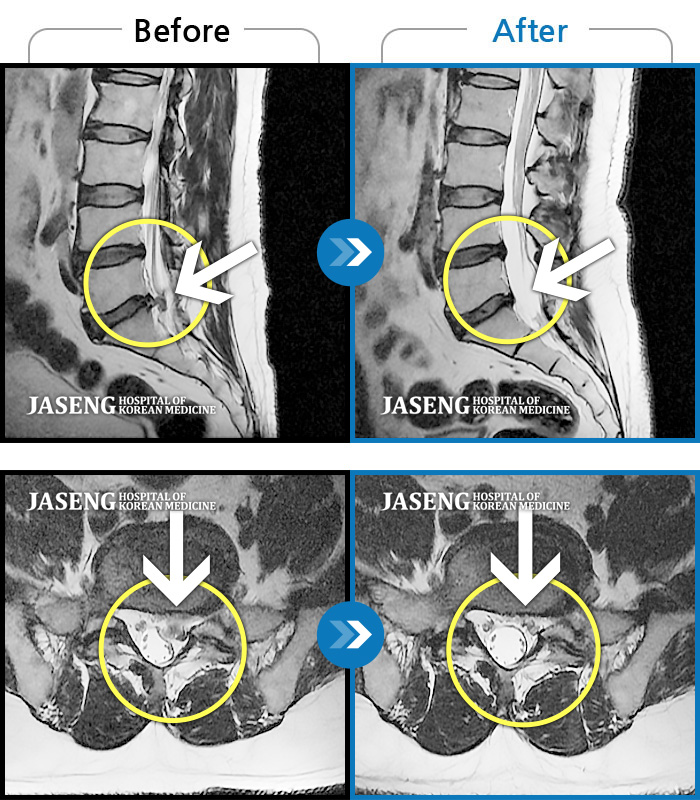

MRI 치료사례

좌측 하지 저림 증상